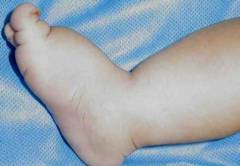

Отеки

У новорожденных с синдромом Шерешевского-Тёрнера наблюдаются специфические отеки, называемые лимфедемой, чаще всего в области стоп. При рождении этот симптом может быть едва заметен, но с ростом ребенка становится более выраженным. При значительном отеке кожа на стопах натянута, а ножки выглядят пухлыми, несмотря на низкий общий вес. Ногти маленькие, деформированные и вдавленные. Лимфедема связана с аномалиями развития лимфатических сосудов, некоторые из которых могут быть сужены с рождения, что затрудняет отток лимфы.

Отек становится заметнее, когда ребенок начинает делать первые шаги. Под действием силы тяжести лимфа скапливается в области стоп и иногда в нижней части голеней. Если у малыша есть врожденный порок сердца или аномалии крупных сосудов, отеки могут проявляться ярко сразу после рождения. Лимфедема в различных формах наблюдается более чем у половины новорожденных с синдромом Шерешевского-Тёрнера.